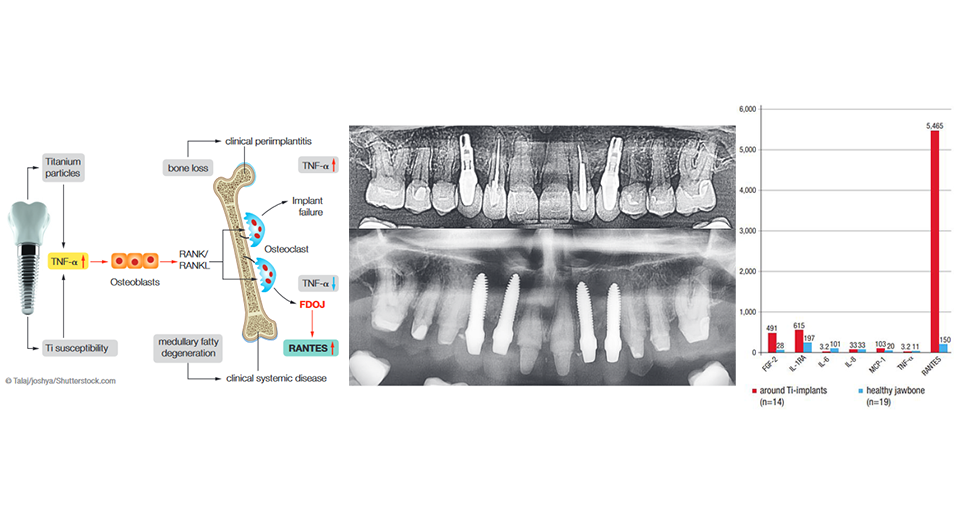

Why titanium implants create silent inflammation in jawbone